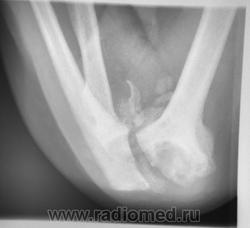

КСС. Артропатия. Сирингомиелия. +

Артропатия.  Сирингомиелия.

Продолжение.